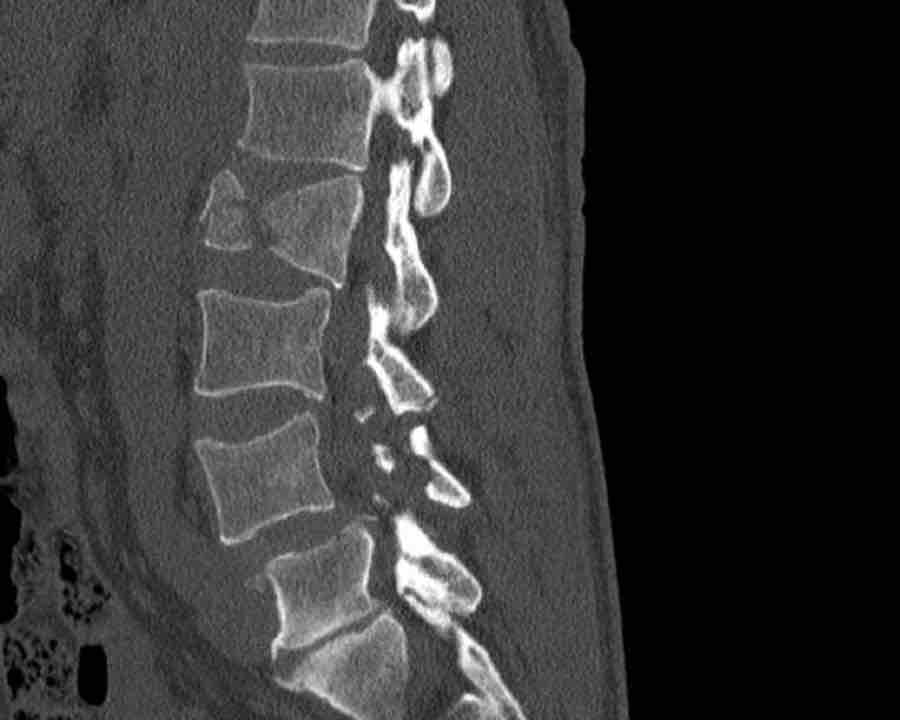

Type A / Compression injury

If it is not a type C or B injury, then the next question is, whether it is a type A compression injury.

Compression injuries are fractures of the vertebral bodies and are classified as:

- A1 fracture of one endplate.

- A2 split fracture where both endplates are involved.

- A3 incomplete burst fracture, where the posterior wall and one endplate are involved

- A4 complete burst fracture, where the posterior wall and both of the endplates are involved.